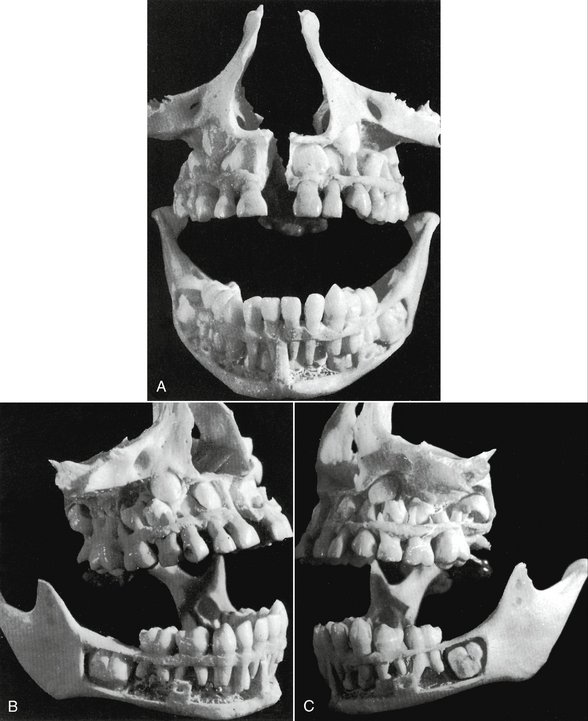

Development

Primary teeth start to form during the embryonic phase of human life. The development of primary teeth starts at the sixth week of tooth development as the dental lamina. This process starts at the midline and then spreads back into the posterior region. By the time the embryo is eight weeks old, there are ten buds on the upper and lower arches that will eventually become the primary (deciduous) dentition. These teeth will continue to form until they erupt in the mouth. In the prima…